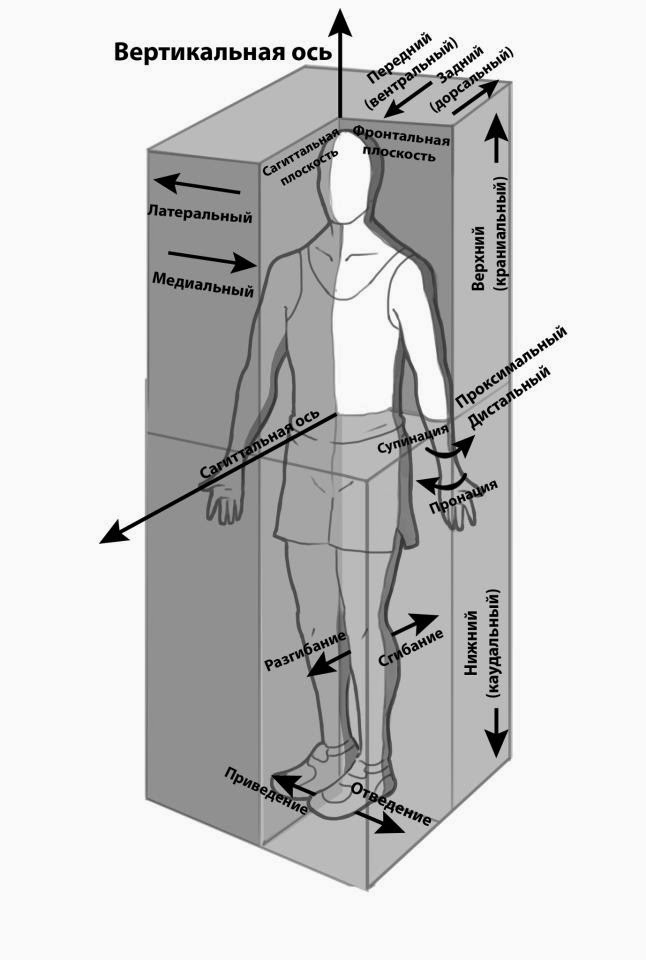

Диаграммы и схемы движения в суставах человека